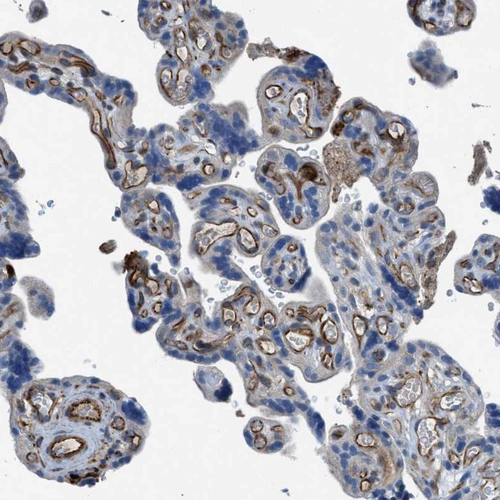

Immunohistochemical staining of human colon shows moderate cytoplasmic positivity in glandular cells.